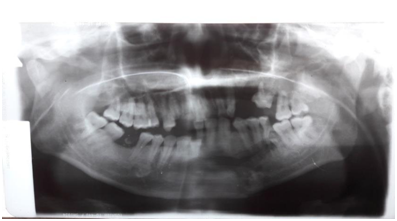

Figure 2 Post-operative Panoramic X-ray. The miniplate lies over the realigned condyle on the left.

The post-operative panoramic x-ray. Showed the occlusion and the realignment of the condylar neck fracture on the right with the long titanium plate in place. The vertical dimension of the right mandibular ramus very nearly approximates the height of the left side .